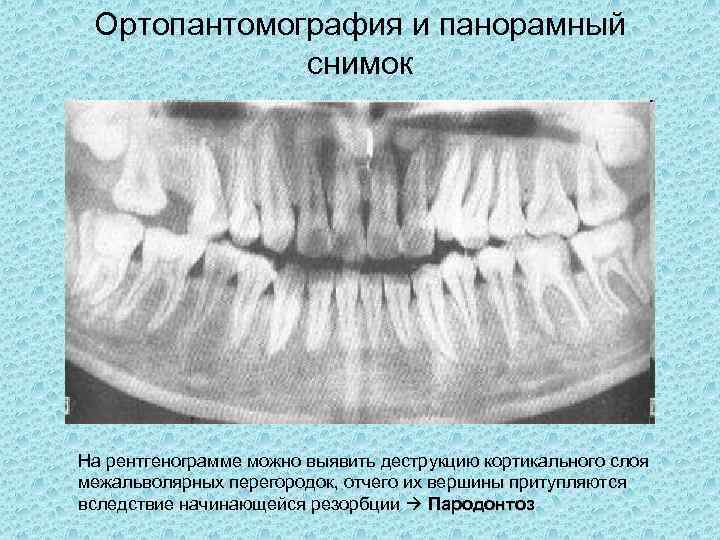

Медицинские Исследования: Кортикальная Пластинка на ОПТГ

Раздел: Кадры-подсказки